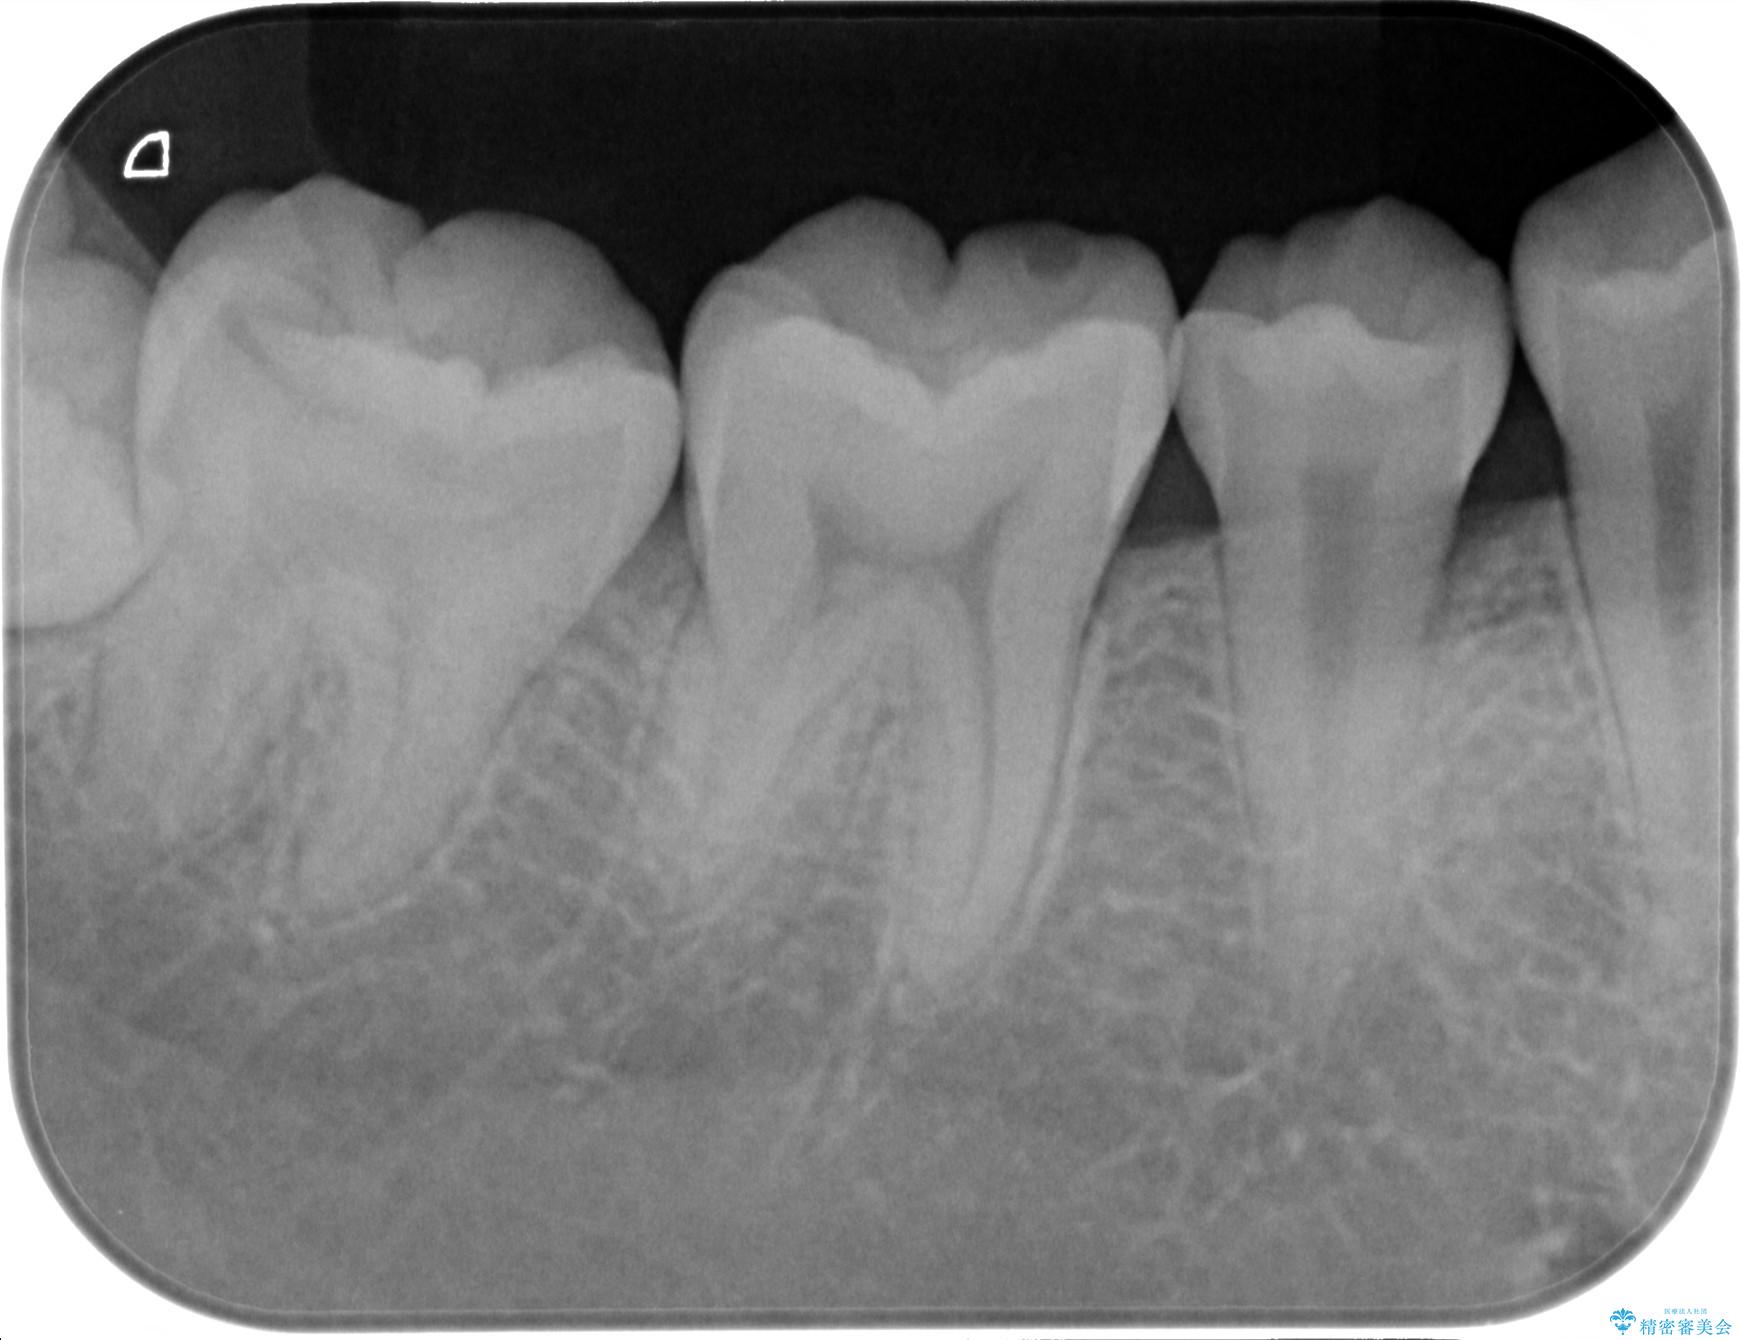

- 検査の結果虫歯が見つかった患者様です。

親知らずを抜歯してから虫歯を除去した後、ゴールドの詰め物で修復します。

比較的大きな虫歯でしたがゴールドでの修復にすることで歯の削る量を抑え、精度の高い治療を行うことができました。